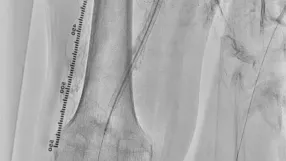

過去にSFAに留置された総長約35 cmの3本のBMSの入口部からの閉塞(動画1)近位端はSFA入口部から1 cm程度の健常部があり、遠位端は膝窩動脈近位部(P1)で側副血行流入部まで1 cmの余白がある。対側山越えアプローチで6 Frガイディングシースを挿入して治療を開始した。ステント外を通過しないように0.035 inchのガイドワイヤーを選択すると容易に遠位部へ到達することが出来た(動画2)。この手ごたえから血栓性病変であることが予想された。持続吸引カテーテルを用いて何度か血栓吸引を行ったが血流は再開しなかった(動画3)。

血管内超音波(IVUS)を行うとガイドワイヤーはステントの中心部を通過していたが、予想通り病変内には大量の血栓が堆積していた(動画4)。7 mmのバルーンで拡張したのち、ステント遠位端より2 cm程度離れた遠位の健常部にhealthy landingをとって(動画5)バイアバーン® ステントグラフト6 × 250 mmを留置した。近位側はステント近位端より1 cm程度離れたSFA入口部の健常部にhealthy landingをとって(動画6)バイアバーン® ステントグラフト7 × 150 mmを留置した。上下端とも既存のステントより外側にランディングをとること、ステントグラフトの電子添文の「使用上の注意」にあたる主要な側枝に注意して、大腿深動脈(DFA)や側副血行の流入部にかからないよう留意した。後拡張は血栓の上下方向へのprotrusionを防ぐ目的で先に遠位端、近位端の順に高圧バルーンで拡張し健常部血管壁への圧着をとった。ステントグラフトの中間部への後拡張はそのあとに続いて行った。最終造影で末梢まで塞栓がないことを確認して終了した(動画7)。